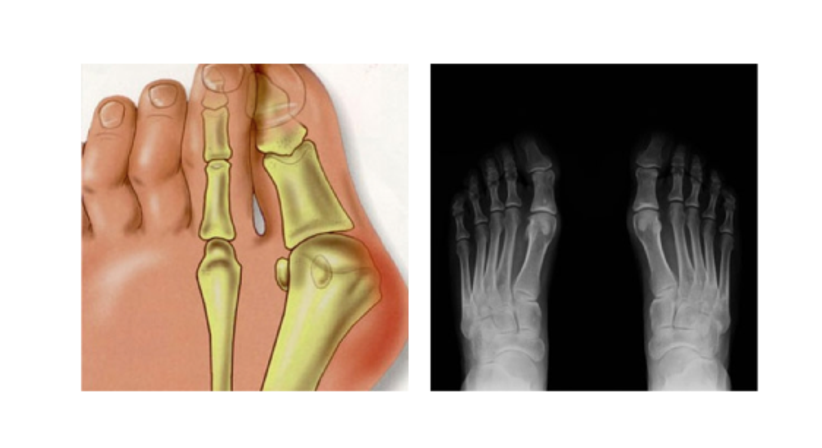

Hallux valgus

ist eine der häufigsten Fehlbildungen der Zehen. Er entsteht meistens durch das dauerhafte Tragen zu enger oder unbequemer Schuhe. Deshalb leiden Frauen auch deutlich öfter unter einem Hallux valgus als Männer. Die Entstehung eines Ballenzehs, wie die Fehlstellung der Großzehe auch genannt wird, kann aber auch durch ein schwaches Bindegewebe, häufiges Stehen oder Rheuma begünstigt werden. Beim Hallux valgus verschiebt sich der Mittelfußknochen nach außen, wo er einen Ballen ausbildet, der bei manchen Patienten gerötet und geschwollen sein kann. Der große Zeh knickt nach innen zu den mittleren Zehen ab. Bei Berührung haben Patienten Schmerzen in der Großzehe, die auch bis in die kleinen Zehen ausstrahlen können.